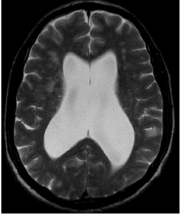

Homem de 70 anos relata quadro de alteração de marcha com base alargada, lentificação e quedas que se iniciou nos últimos 4 meses, seguido de apatia, irritabilidade, déficit de memória, confusão mental, desorientação. Nas últimas semanas vem apresentando urgência urinária. É solicitado exame de imagem, a seguir.

A hipótese diagnóstica é